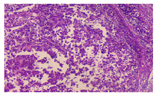

入院后完善相关检查,给予护肝、营养支持等相关对症治疗,经过我院多学科团队(multi-disciplinary team,MDT)会诊认为,虽然患者手术意愿强烈,但肿瘤负荷大,且门静脉主干及左右支都存在癌栓,如进行手术治疗患者不获益的可能性较大,可先给予转化治疗。经充分知情同意后,于2021年10月20日至2022年3月21日行派安普利单抗200 mg免疫治疗(静脉滴注,每3周1次),同时于2021年10月20日至2022年4月4日联合口服盐酸安罗替尼12 mg(服用2周停1周)靶向治疗,其中在2021年10月25日行肝动脉灌注化疗,后患者无法耐受拒绝再次肝动脉灌注化疗治疗。每3个免疫治疗周期复查一次,2021年12月26日CT检查结果提示:肝脏4段段病灶范围较前缩小,密度较前减低,门静脉主干内血栓范围较前缩小,余无特殊。2022年3月21日CT检查结果提示:肝脏4段段病灶范围较前缩小,密度较前减低,左肝外叶新增无强化低密度灶较前缩小,门静脉主干内血栓基本吸收,余无特殊(图2)。甲胎蛋白和异常凝血酶原明显降低(图3)。治疗过程中2022年1月19日出现低钾电解质紊乱,予以补钾维持水电解质平衡。2022年3月21日复查达到部分缓解,但出现甲状腺功能减低,经院内MDT讨论本周期后停药派安普利单抗,口服甲状腺素片,定期复查甲状腺功能,待正常择期行左半肝切除术。2022年5月4日MRI检查结果提示:原S4占位较前明显缩小,较大横面约72 mm×43 mm,门静脉内癌栓较前明显减少,2022年5月4日甲状腺功能正常后,完善术前准备,评估肝功能为Child-pugh分级A级,吲哚菁绿排泄实验:6.8%,测量残肝体积为:60.5%。于2022年5月10日行左半肝切除+胆囊切除胆道探查+胆肠内引流+门静脉节段切除重建+膈肌部分切除术。术后病理学检查结果示:(1)送检肝肿块切除标本,多个肿物内大部分为凝固性坏死,仅残留一小灶癌(镜下最大径3 mm),为肝细胞癌Ⅲ级,并可见异物巨细胞反应及蓝染无结构物,符合肝动脉化疗栓塞术后改变。肿物紧邻被膜下,未累及膈肌,肝切缘净。(2)慢性胆囊炎,胆囊结石,胆囊颈部淋巴结反应性增生。(3)12组淋巴结镜下可见纤维脂肪组织,伴炎细胞浸润,未见癌。(4)门静脉壁未见癌,癌栓已完全坏死。(5)胆管壁慢性胆管炎,纤维组织增生。免疫组化(图4):CA19-9(-)、CD34(血管+)、CK7(-)、CK8/18(+)、Glypica n﹣3(+)、Arg-1(+)、Hepatocyte(+)、CEA(-)、Ki67(+,25%)、p53(-)、Syn(-)、GS-6(+)。